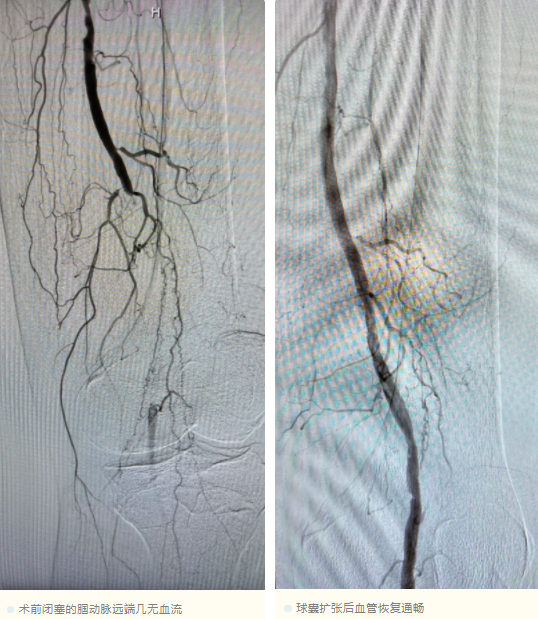

据了解,患者因左下肢间歇性跛行数月,近期左足趾出现坏疽并伴有持续性疼痛,行走与睡眠受到严重影响,于是紧急前往永福县人民医院就诊。经下肢血管造影检查,患者被确诊为左下肢腘动脉闭塞。血管的堵塞会导致下肢血运减少,进而使患者创面迁延不愈并静息痛加重,极大地影响患者的正常生活。

手术当天,血管外科执行副主任王伦常、行政副主任姚松良抵达后,再次与永福县人民医院外科团队开展术前讨论,细化手术流程与风险应对预案。考虑到县医院DRG及患者的经济条件,团队选择真腔通过闭塞病变,并采取POBA(经皮腔内球囊血管成形术)加药物球囊方案,无需支架置入,在保证治疗效果的同时满足多方需求。术后,患者当即感到患肢皮温明显回升,疼痛显著减轻,持续性疼痛症状显著缓解,肢体血供得到了有效改善。